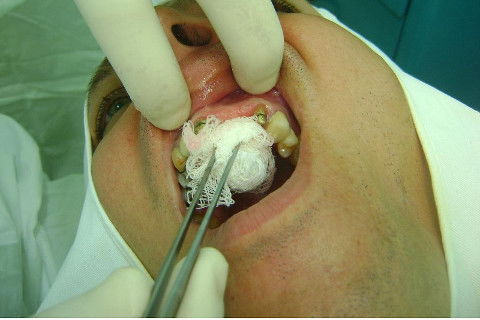

Cirurgia realizada hoje de manhã...No planejamento percebi medindo espessura do rebordo com especímetro que as medidas não estavam muito boas, ou o ideal, em torno de 4,5 a 5 mm ate´o terço médio do rebordo e melhorava no final, com 6 a 7 mm. Optei então por uma pequena expansão usando os expansores rosqueáveis. Aconteceu uma pequena fenestração na hora da fixação dos implantes, especialmente na região do 22 que fraturou o início da tábua óssea, mas não me preocupei porque não foi mais do que 2 mm de fratura em direção apical, o implante ficou infraósseo e com boa estabilidade (60 N no 21 e 40 N no 22). Esta fratura tb não deixou osso completamente solto, foi do tipo galho verde, deixei em posição e suturei normalmente. Só não fiz e nem estava planejado carga imediata mesmo, mais pelo motivo da oclusão inadequada do caso.

Fotos do caso